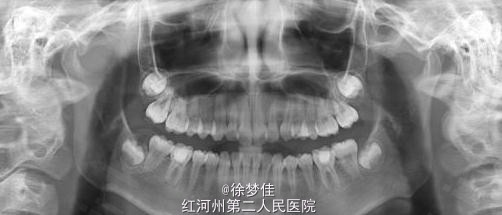

患者女,14岁,于院外行左下后牙根管治疗,断针,无法取出,遂就诊。

左下6近中根管断针X-P,断针长度约4MM, 根尖慢性炎症